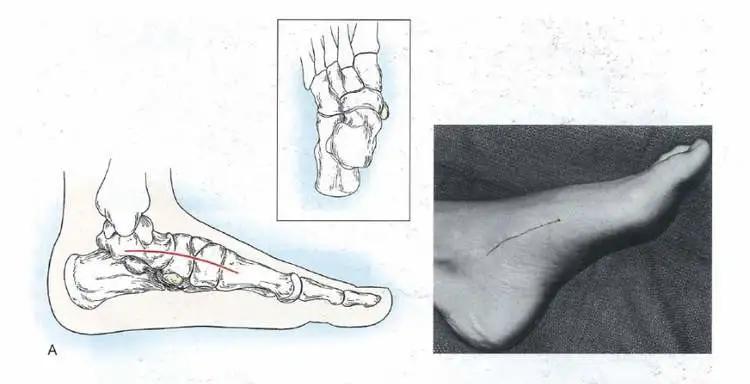

在保守治疗无效的情况下,可考虑手术治疗。现阶段效果确切的手术方式是:副舟骨切除+胫后肌止点重建。手术效果确切,三个月后可正常活动。

如图所示,手术切口很小,术后配合应用祛疤药,基本看不出瘢痕。